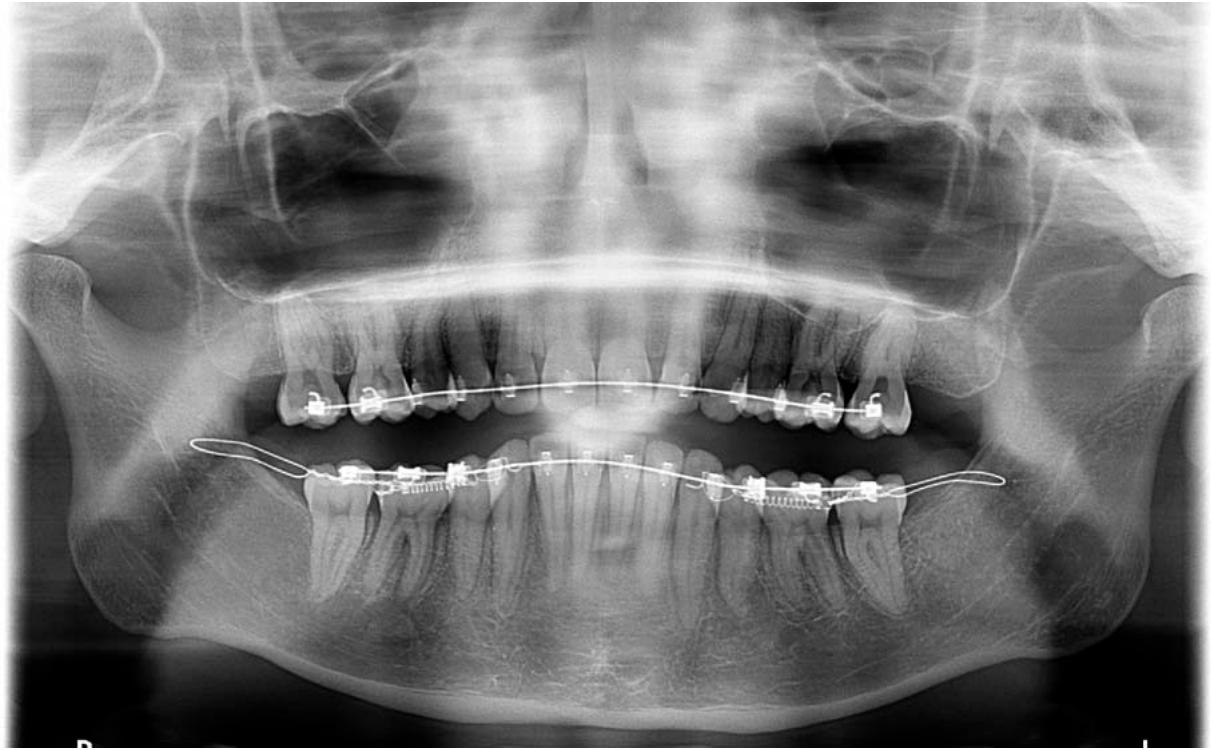

Orthopantomographie prise lors de la mise en traction du système. Les ressorts sont connectés entre les Abalakov et les canines mandibulaires en traction directe.